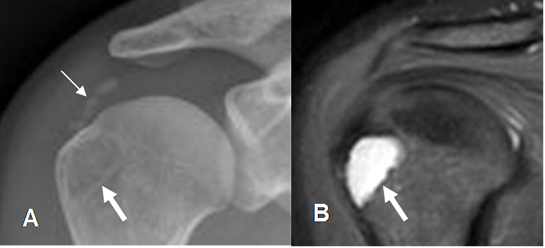

Determinar la calidad de la cabeza humeral, es muy importante para planear una cirugía de manguito. Debe valorarse la presencia de edema oseo, quistes subcondrales, etc. (16). (Fig 157).

Fig 157. Valoración Pre Qx.

A: Rx AP y B: RM coronal en STIR. Calcificaciones sobre la topografía del tendón supraespinoso, por tendinitis crónica. Sobre la tuberosidad mayor se aprecia imagen radiolúcida y de aspecto benigno, que corresponde a lesión quística confirmada con la RM.